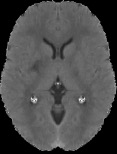

Accurate infarct segmentation in non-contrast CT (NCCT) images is a crucial step toward computer-aided acute ischemic stroke (AIS) assessment. In clinical practice, bilateral symmetric comparison of brain hemispheres is usually used to locate pathological abnormalities. Recent research has explored asymmetries to assist with AIS segmentation. However, most previous symmetry-based work mixed different types of asymmetries when evaluating their contribution to AIS. In this paper, we propose a novel Asymmetry Disentanglement Network (ADN) to automatically separate pathological asymmetries and intrinsic anatomical asymmetries in NCCTs for more effective and interpretable AIS segmentation. ADN first performs asymmetry disentanglement based on input NCCTs, which produces different types of 3D asymmetry maps. Then a synthetic, intrinsic-asymmetry-compensated and pathology-asymmetry-salient NCCT volume is generated and later used as input to a segmentation network. The training of ADN incorporates domain knowledge and adopts a tissue-type aware regularization loss function to encourage clinically-meaningful pathological asymmetry extraction. Coupled with an unsupervised 3D transformation network, ADN achieves state-of-the-art AIS segmentation performance on a public NCCT dataset. In addition to the superior performance, we believe the learned clinically-interpretable asymmetry maps can also provide insights towards a better understanding of AIS assessment. Our code is available at https://github.com/nihaomiao/MICCAI22_ADN.